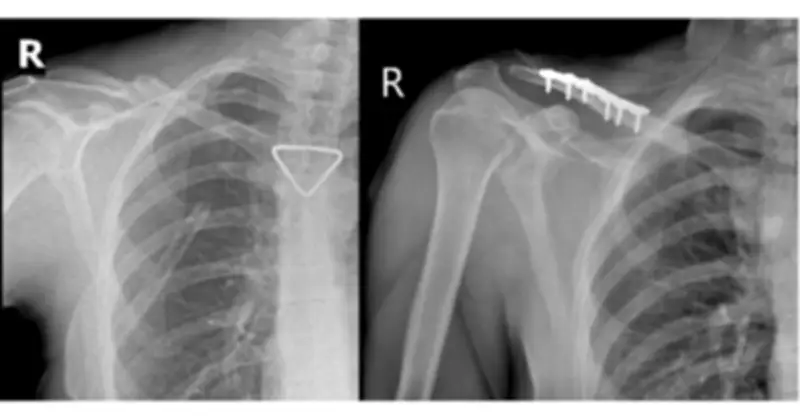

Ngay khi tiếp nhận, các bác sĩ đã khẩn trương thực hiện CT scan lồng ngực và mạch máu khẩn cấp. Kết quả cho thấy bệnh nhân bị tràn khí màng phổi phải lượng nhiều, gây chèn ép phổi, kèm theo gãy cung bên xương sườn thứ 2, 3, 4 phải và gãy phức tạp 1/3 giữa xương đòn phải với di lệch nhiều và mảnh rời. Trước nguy cơ suy hô hấp nặng, ê-kíp Khoa Phẫu thuật Tim – Lồng ngực – Mạch máu đã tiến hành đặt dẫn lưu màng phổi phải cấp cứu, do TS-BS Đồng Đức Hưng trực tiếp thực hiện.